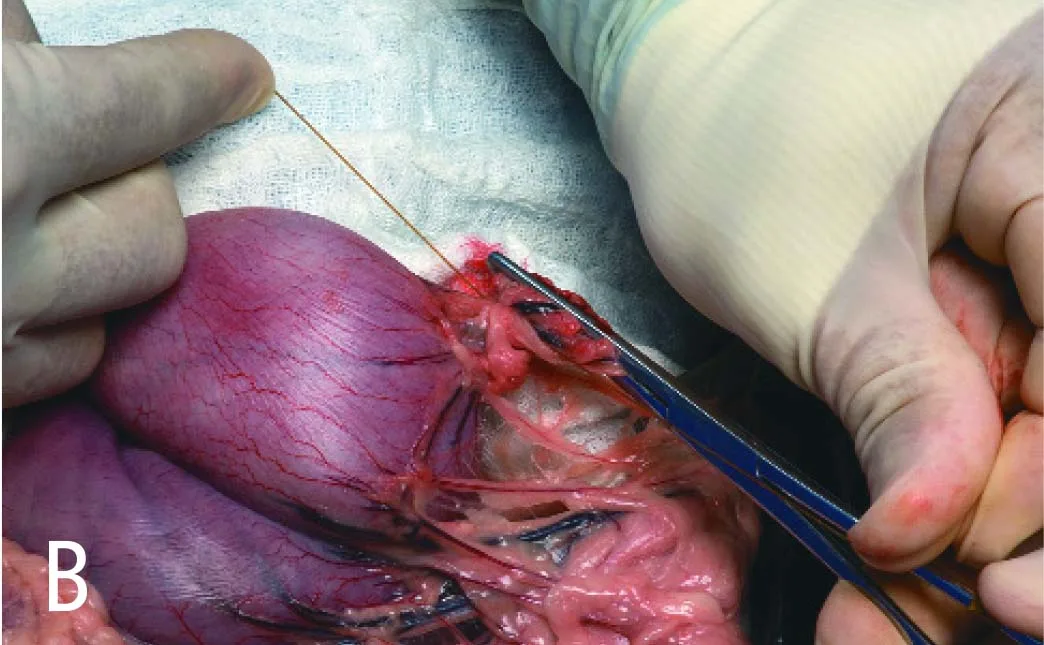

Securely double-ligate the pedicles and remove the forceps. Ligatures are ideally placed several millimeters or more from the cut pedicle edge to allow tissue to "mushroom" and help prevent ligature slippage. In A, a ligature is shown encircling the short gastric artery pedicle just below forceps #1. Notice the deformed "spread out" pedicle that will not allow a tight ligature to be formed if the forceps is not released. In B, the pedicle is constricted after the forceps is removed and the ligature tightened within the previously crushed area.